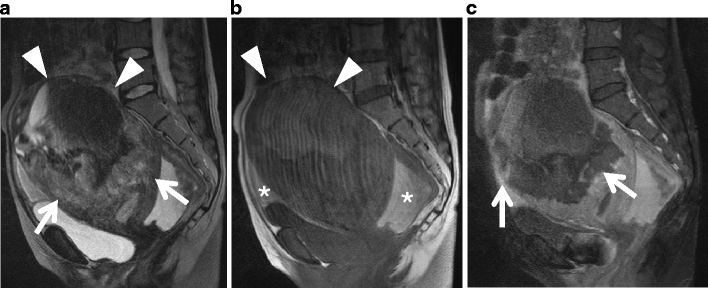

Undifferentiated stromal sarcoma in a 22-year-old female who presented with acute abdomen due to uterine rupture. a Sagittal T2-weighted image demonstrates an ill-defined myometrial mass of heterogeneous appearance in the anterior wall (arrows). The upper portion of the tumor containing fluid-fluid level represents hemorrhagic necrosis within the tumor (arrowheads). b T1-weighted image demonstrates increased signal intensity corresponding to the area of hemorrhagic necrosis (arrowheads). Hemorrhagic ascites of increased signal intensity also is present in the Douglas fossa and uterovesical fossa (asterisks). c Postcontrast T1-weighted image with fat suppression demonstrates heterogeneous enhancement within the solid component of the tumor (arrows)